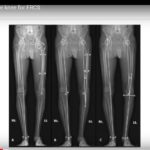

Functional Alignment of Knee

Courtesy: Dr Eugene E K, Ashok Shyam, Ortho TV Functional Alignment in Knee Replacement Surgery Introduction Alignment strategies in total knee replacement have evolved significantly over the years. Many surgeons initially adopted mechanical alignment, which has been the traditional and widely practiced method for several decades. Over time, alternative approaches such as kinematic alignment and […]